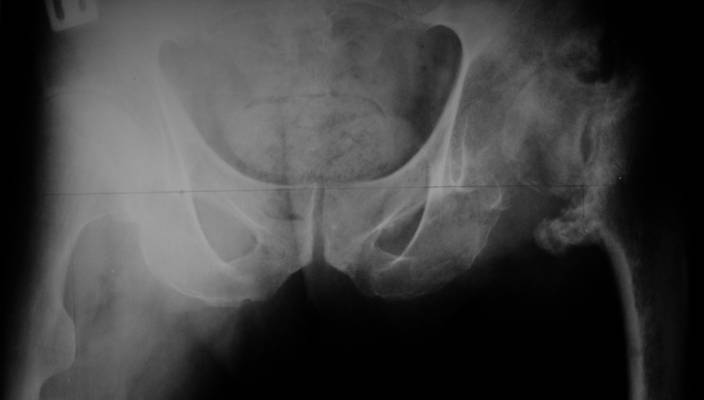

AV> опираясь на стул. На ногу не наступает. Укорочение 8 см. Иногда

А за счет чего такое укорочение? По снимку не видно соответствующего дефекта. Ну плюс приводящая контрактура - но все равно как-то уж больно много. Может, сделать снимки и таза обзорный с обоими проксимальными отделами бедра, и коенный суставов с приложенной линейкой какой?

Судя по снимку, максимум истинное укорочение около 4 см, что может быть коррегировано интраоперационно. Вопрос в другом: куда ставить ацетабулярный компонент в истинную или во вновь сформированную ( впадина диспластичная).

Невозможно не согласиться с Анатолием, чтобы заниматься адекватным планированием как минимум прямая проекция таза должна быть сделана, как

The X ray that you provided does not show 8 cm of shortening. Perhaps you could send one showing the whole pelvis and proximal femurs.

I agree with Dr Eid's comments. The origin of the 8 cm leg length difference is a puzzle. Is this a clinical measurement? In that case contracture of the joint might affect the measurement. Can we see an AP pelvis to include both hip joints (including a calibration object with a known length) so that the difference in leg lengths that can be ascribed to the hip deformity and bony reabsorption can be measured. This sort of xray will help with templating for the TJR also. I would be very tempted to do a one stage procedure and accept some shortening. Shoe lifts should take care of a 3-4 cm difference.

До травмы проблем с ногой не было. Укорочения, болей и т.п. не отмечал. Сегодня перемерял укорочение - меньше 7 см намерять не

По уровню малых вертелов (с учетом рентгеновского увеличения) получается 5 см. Клинически ногу низвести путем тракции невозможно. Из движений - сгибание до 40*, остальные движения "символические".

Ортопедическое укорочение пострадавшей ноги может быть и 7, и 10 см. за счет контрактур в тазобедренном суставе, а вот истинное укорочение, судя по представленным рентгенограммам, вряд ли больше 4 см.